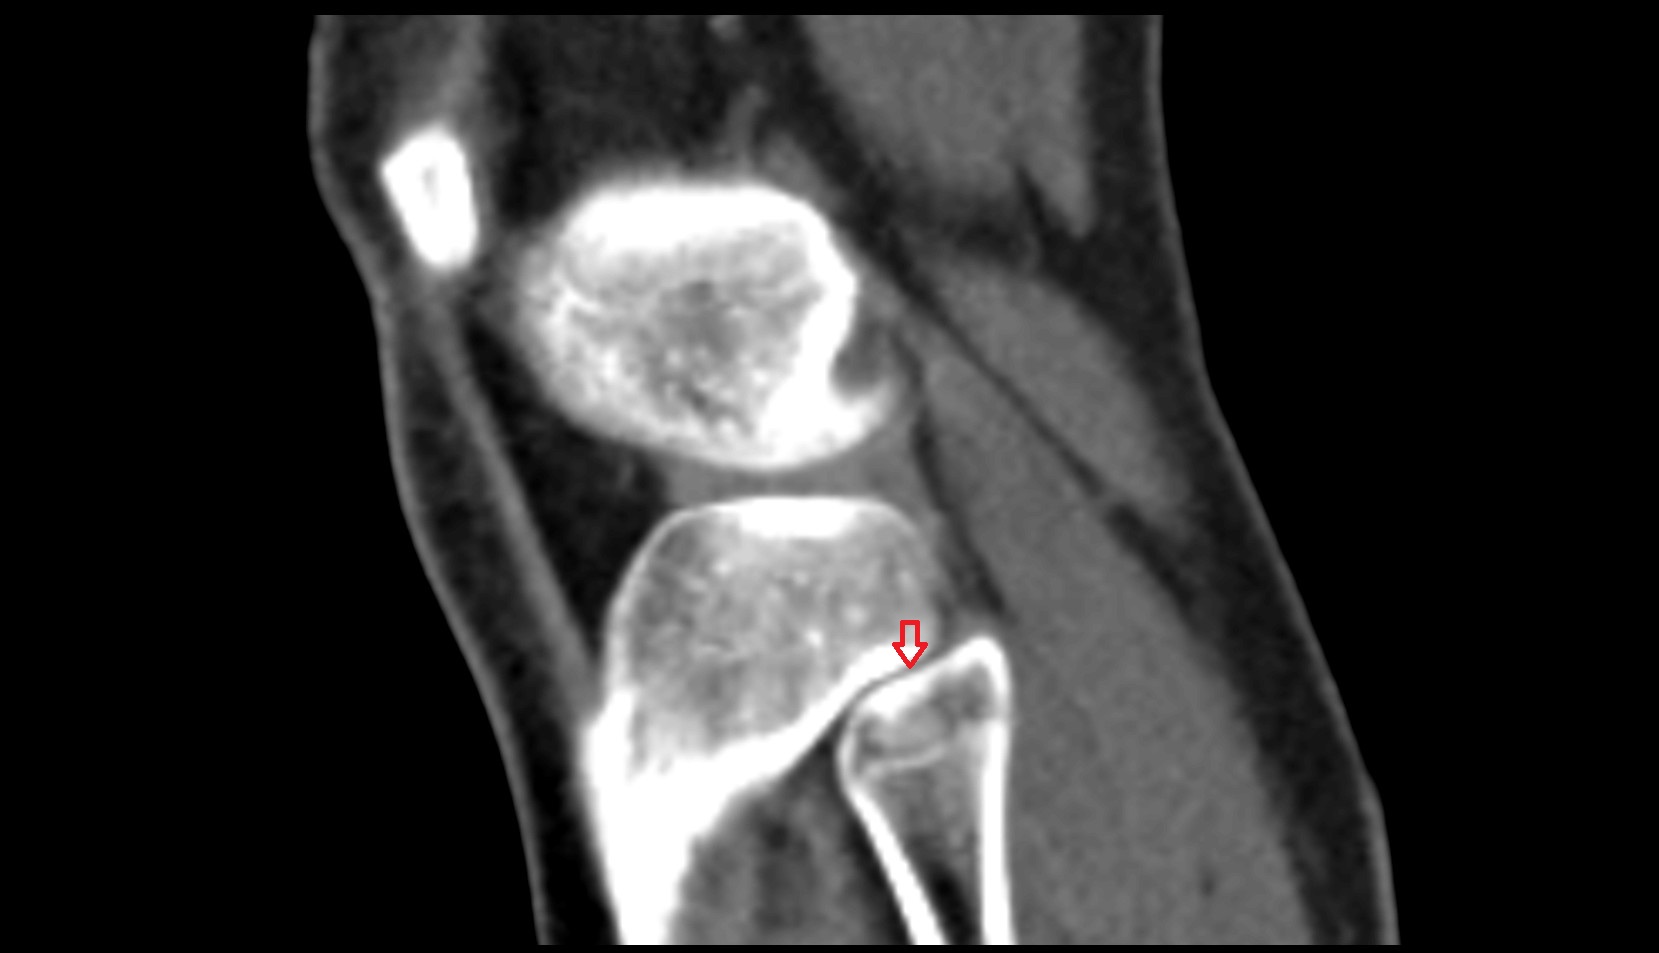

- Knee Joint